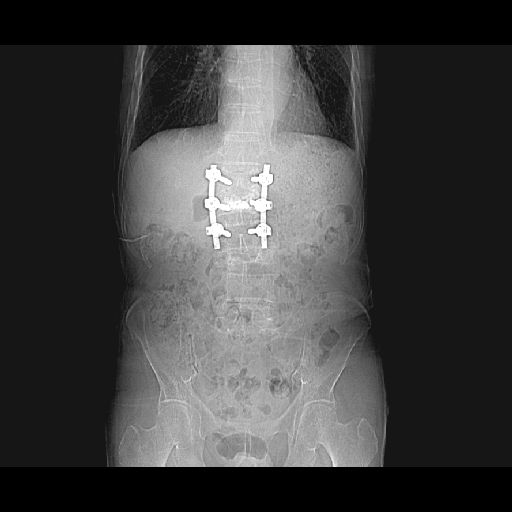

腰椎後方固定術(PLIF)-新小文字病院脊髄脊椎外科治療センターにて87歳になる一人暮らしの父がフェリー船内で転んだことから激しい腰痛に悩まされ、日常生活に支障をきたすようになりました。 「独立行政法人労働者健康福祉機構 総合せき損センター」でブロック注射を受けたのですが、症状はあまり改善されませんでした。 寝たきりを恐れた父は手術を決意。従兄の献身的な病院探しで、高齢にも関わらず手術入院を受諾いただいた「新小文字病院脊髄脊椎外科治療センター」(門司市)で2010/07/25に腰椎後方固定術(PLIF)の手術しました。 普通、4本のスクリュー(ボルト)で固定するのですが、父の場合、6本のボルトを入れることになりました。 3時間近い手術を無事終え、3日目からは少しずつ歩けるようになり、体調も回復傾向。痛みは残っているものの手術前に比べるとずい分楽になったようです。 しかしながら、高齢であるが故に「造骨」に時間がかかるため術後のリハビリが課題です。 固定部分を刺激すると、ボルトが弛むため、

術前術後のレントゲン以下、レントゲン写真を紹介します。「1→」第3腰椎でしょうか、つぶれています。しかし、担当医によればこの部分からの痛みはないようです。 「2→」第1腰椎でしょうか、腹側がささくれています。 又、写真には写っていませんがこの部分の「腰神経叢」滞りがあるようです。 ![]() チタン製のスクリューと固定版を背中側から撮った映像です。 MRで胴体部分を輪切りにした映像です。 縦に3本のスクリューが入れられているのが鮮明に表示されています。 「3→」の部分は避けていた腰椎に人口骨を入れ補強・修正した部分をなります。